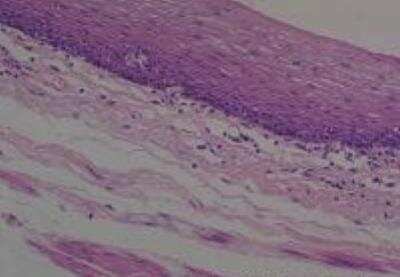

Hematoxylin & Eosin Stain: Human Common Tissue MicroArray (Normal Adjacent) [NBP2-30215] - 01. Stomach